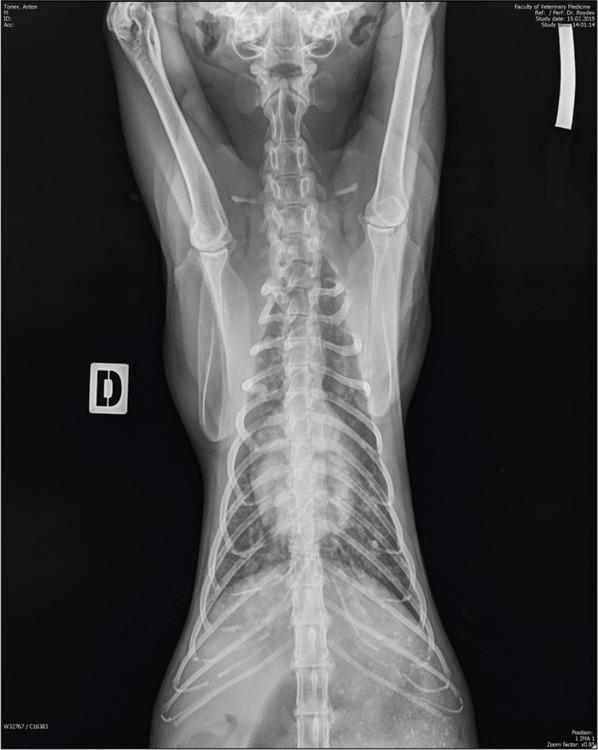

Fig. 1

Fig. 2

Fig. 3

Fig. 4

Fig. 5

Fig. 6

Fig. 7